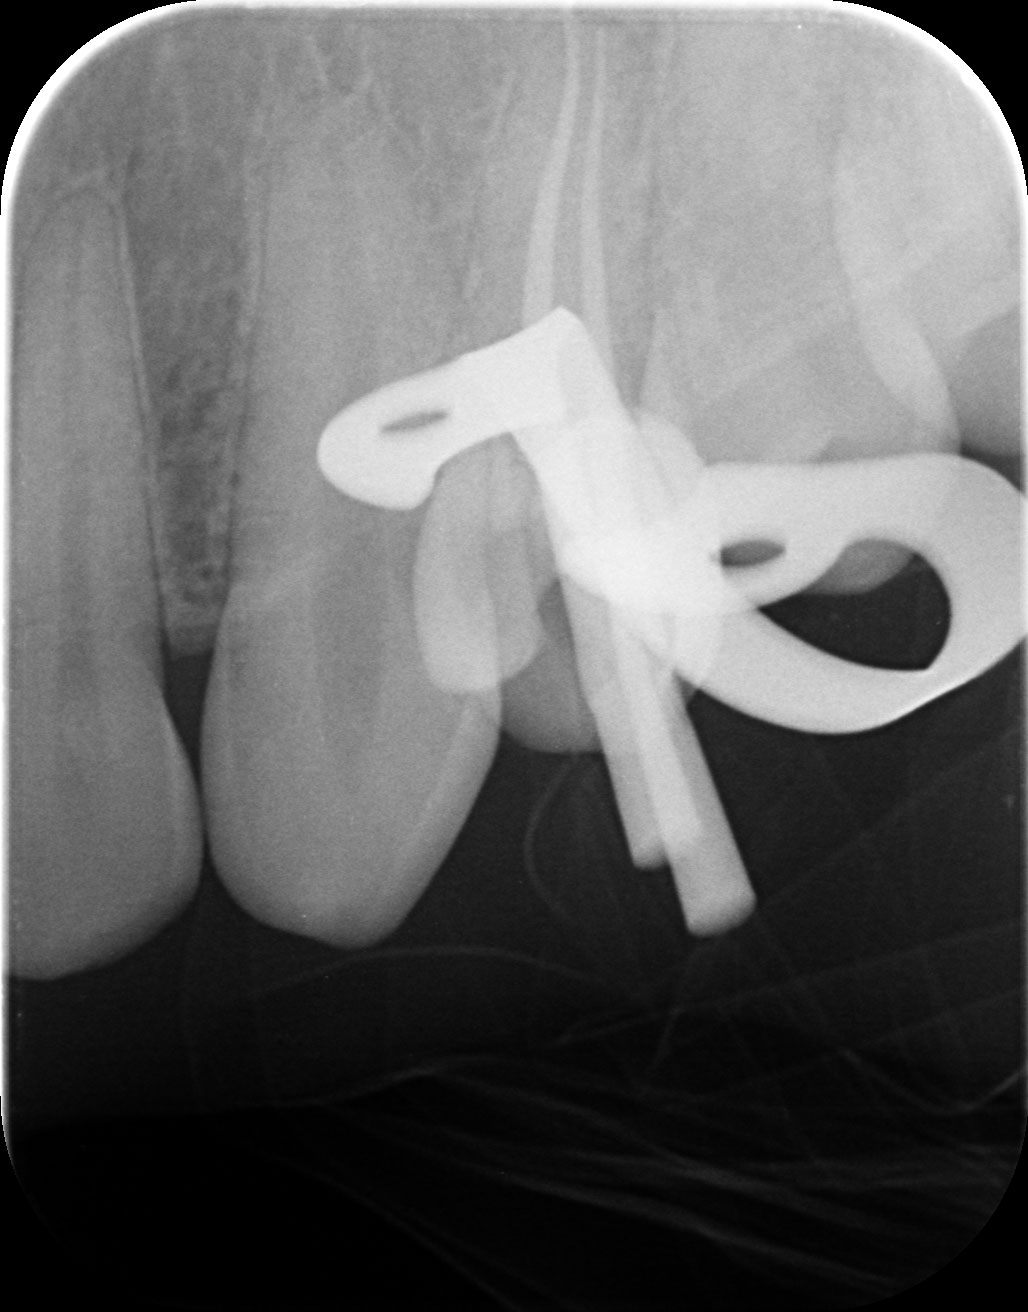

Dantų kanalų gydymas